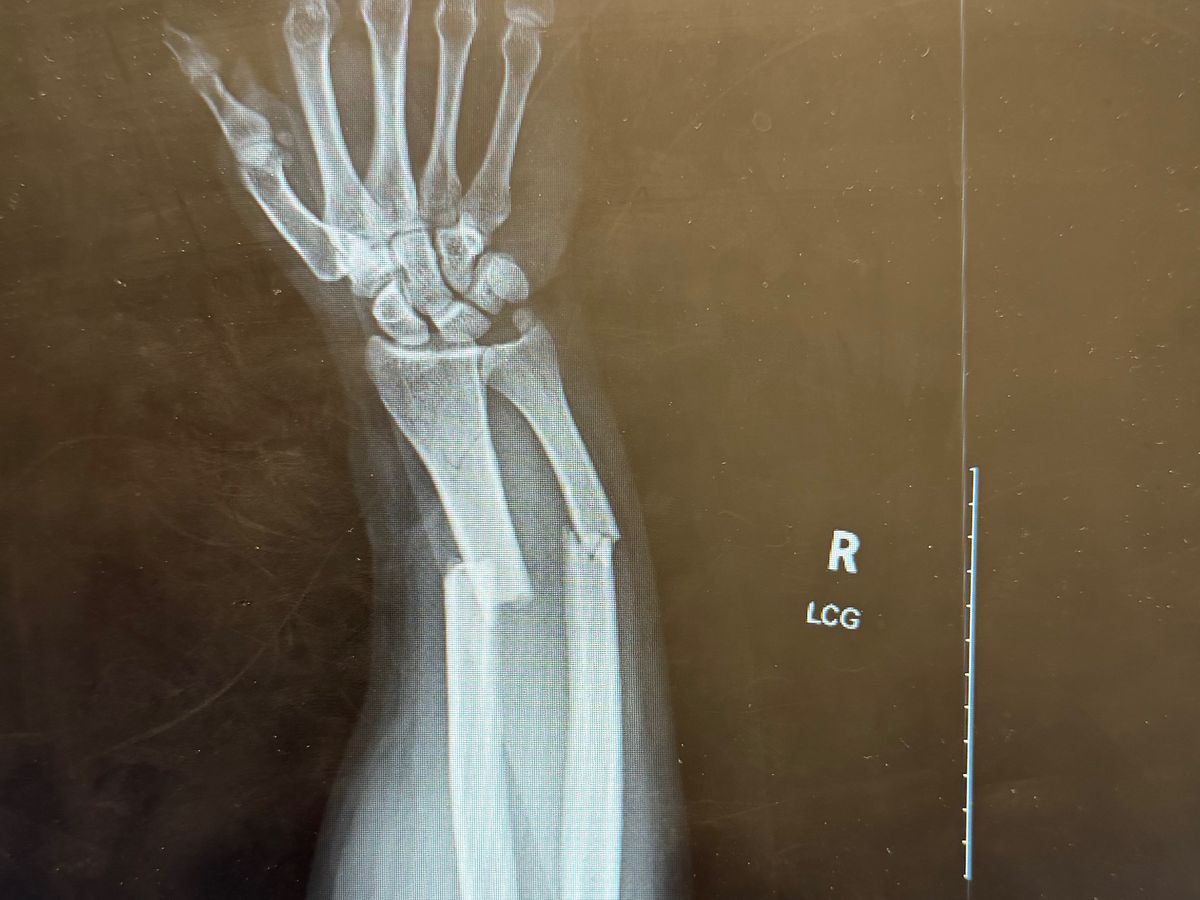

Our friend Rigo was injured during an indoor soccer game on Monday. In a split second, a powerful shot sent the ball flying toward him, and as he tried to protect his face, it struck his right hand with such force that both bones snapped. The injury was severe, and Rigo needed immediate medical attention, including surgery, an ER visit, and an ambulance ride.

Nuestro amigo Rigo se lesionó durante un partido de fútbol sala el lunes. En una fracción de segundo, un potente disparo envió el balón volando hacia él y, al intentar protegerse la cara, le impactó la mano derecha con tanta fuerza que le rompió ambos huesos. La lesión fue grave y Rigo necesitó atención médica inmediata, que incluyó cirugía, una visita a urgencias y un traslado en ambulancia.